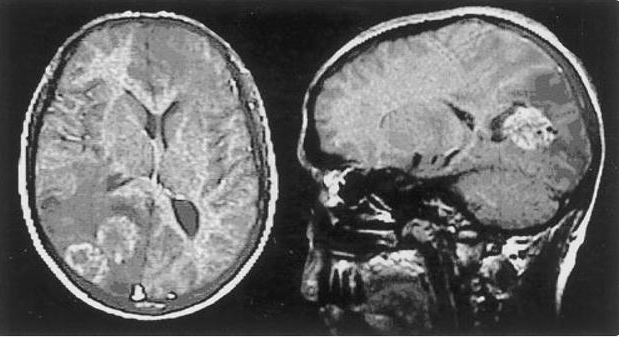

Torbiel u 29-letniego mężczyzny zakażonego Echinococcus

Najczęstszymi gatunkami Echinococcus powodującymi zakażenia u ludzi są E. granulosis i E. multilocularis. E. granulosis powoduje chorobę bąblowca torbielowatego i jest endemiczna w basenie Morza Śródziemnego, na Bliskim Wschodzie i w Ameryce Łacińskiej, natomiast E. multilocularis powoduje chorobę bąblowca pęcherzykowego i jest endemiczna na Alasce, w Europie Środkowej, Turcji i Chinach. Żywicielami ostatecznymi są lisy arktyczne i rude, ale zakażeniu mogą ulec również psy i koty domowe. Po spożyciu przez zwierzę pasożyt szybko przemieszcza się z jelita cienkiego do wątroby, a następnie przez naczynia krwionośne lub limfatyczne do płuc, mózgu, kręgów, osierdzia, nerek lub tkanki okołooczodołowej. Człowiek i owce są żywicielami pośrednimi i zarażają się, połykając jaja wydalane przez zarażone zwierzęta. Większość zakażeń powoduje powstawanie pojedynczych torbieli bąblowca w wątrobie. Zakażenie bąblowcem często pozostaje niewykryte, dopóki powiększenie się torbieli nie wywoła objawów. W miarę wzrostu ciśnienia wewnątrzczaszkowego początkowym subtelnym objawom klinicznym, takim jak ból głowy, towarzyszą także nudności, wymioty i drgawki.1